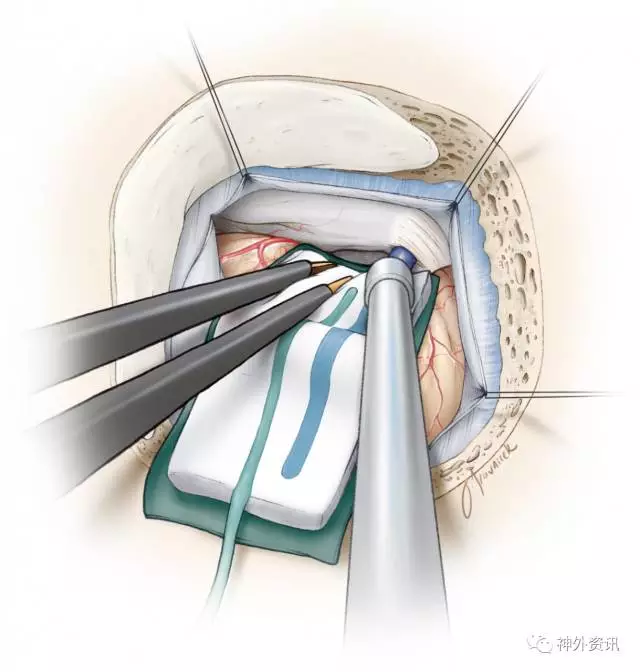

图7. 在岩-幕交界处下部往内下方向牵引小脑。

剪一小片手套(剪成略大于脑棉)作为橡胶垫片,保护小脑半球免受脑棉摩擦所致的潜在的损伤。笔者会将胶片平行且稍低于天幕与岩尖交界处(沟)并朝着岩骨方向下方放置。辨别这些标记以预防:1)小脑上桥静脉意外暴露(或由此产生的撕裂),2)将牵开器直接放到面听神经复合体的下方。

轻柔向内下方牵拉小脑半球,暴露岩上静脉。锐性打开静脉下方的蛛网膜,释放多余脑脊液。为了保护岩静脉及面听神经,应该使其上覆盖的蛛网膜保持完整。

用吸引器轻柔地动态牵拉,在岩上静脉下方往外侧牵拉小脑半球,使静脉略有张力。这种方式足以提供所需的操作空间,极少需要牺牲岩上静脉。灵活使用吸引器有利于选择性暴露必要的手术空间,取得三叉神经REZ区合适的操作角度。避免了使用脑组织牵开器以及岩上静脉的牺牲。